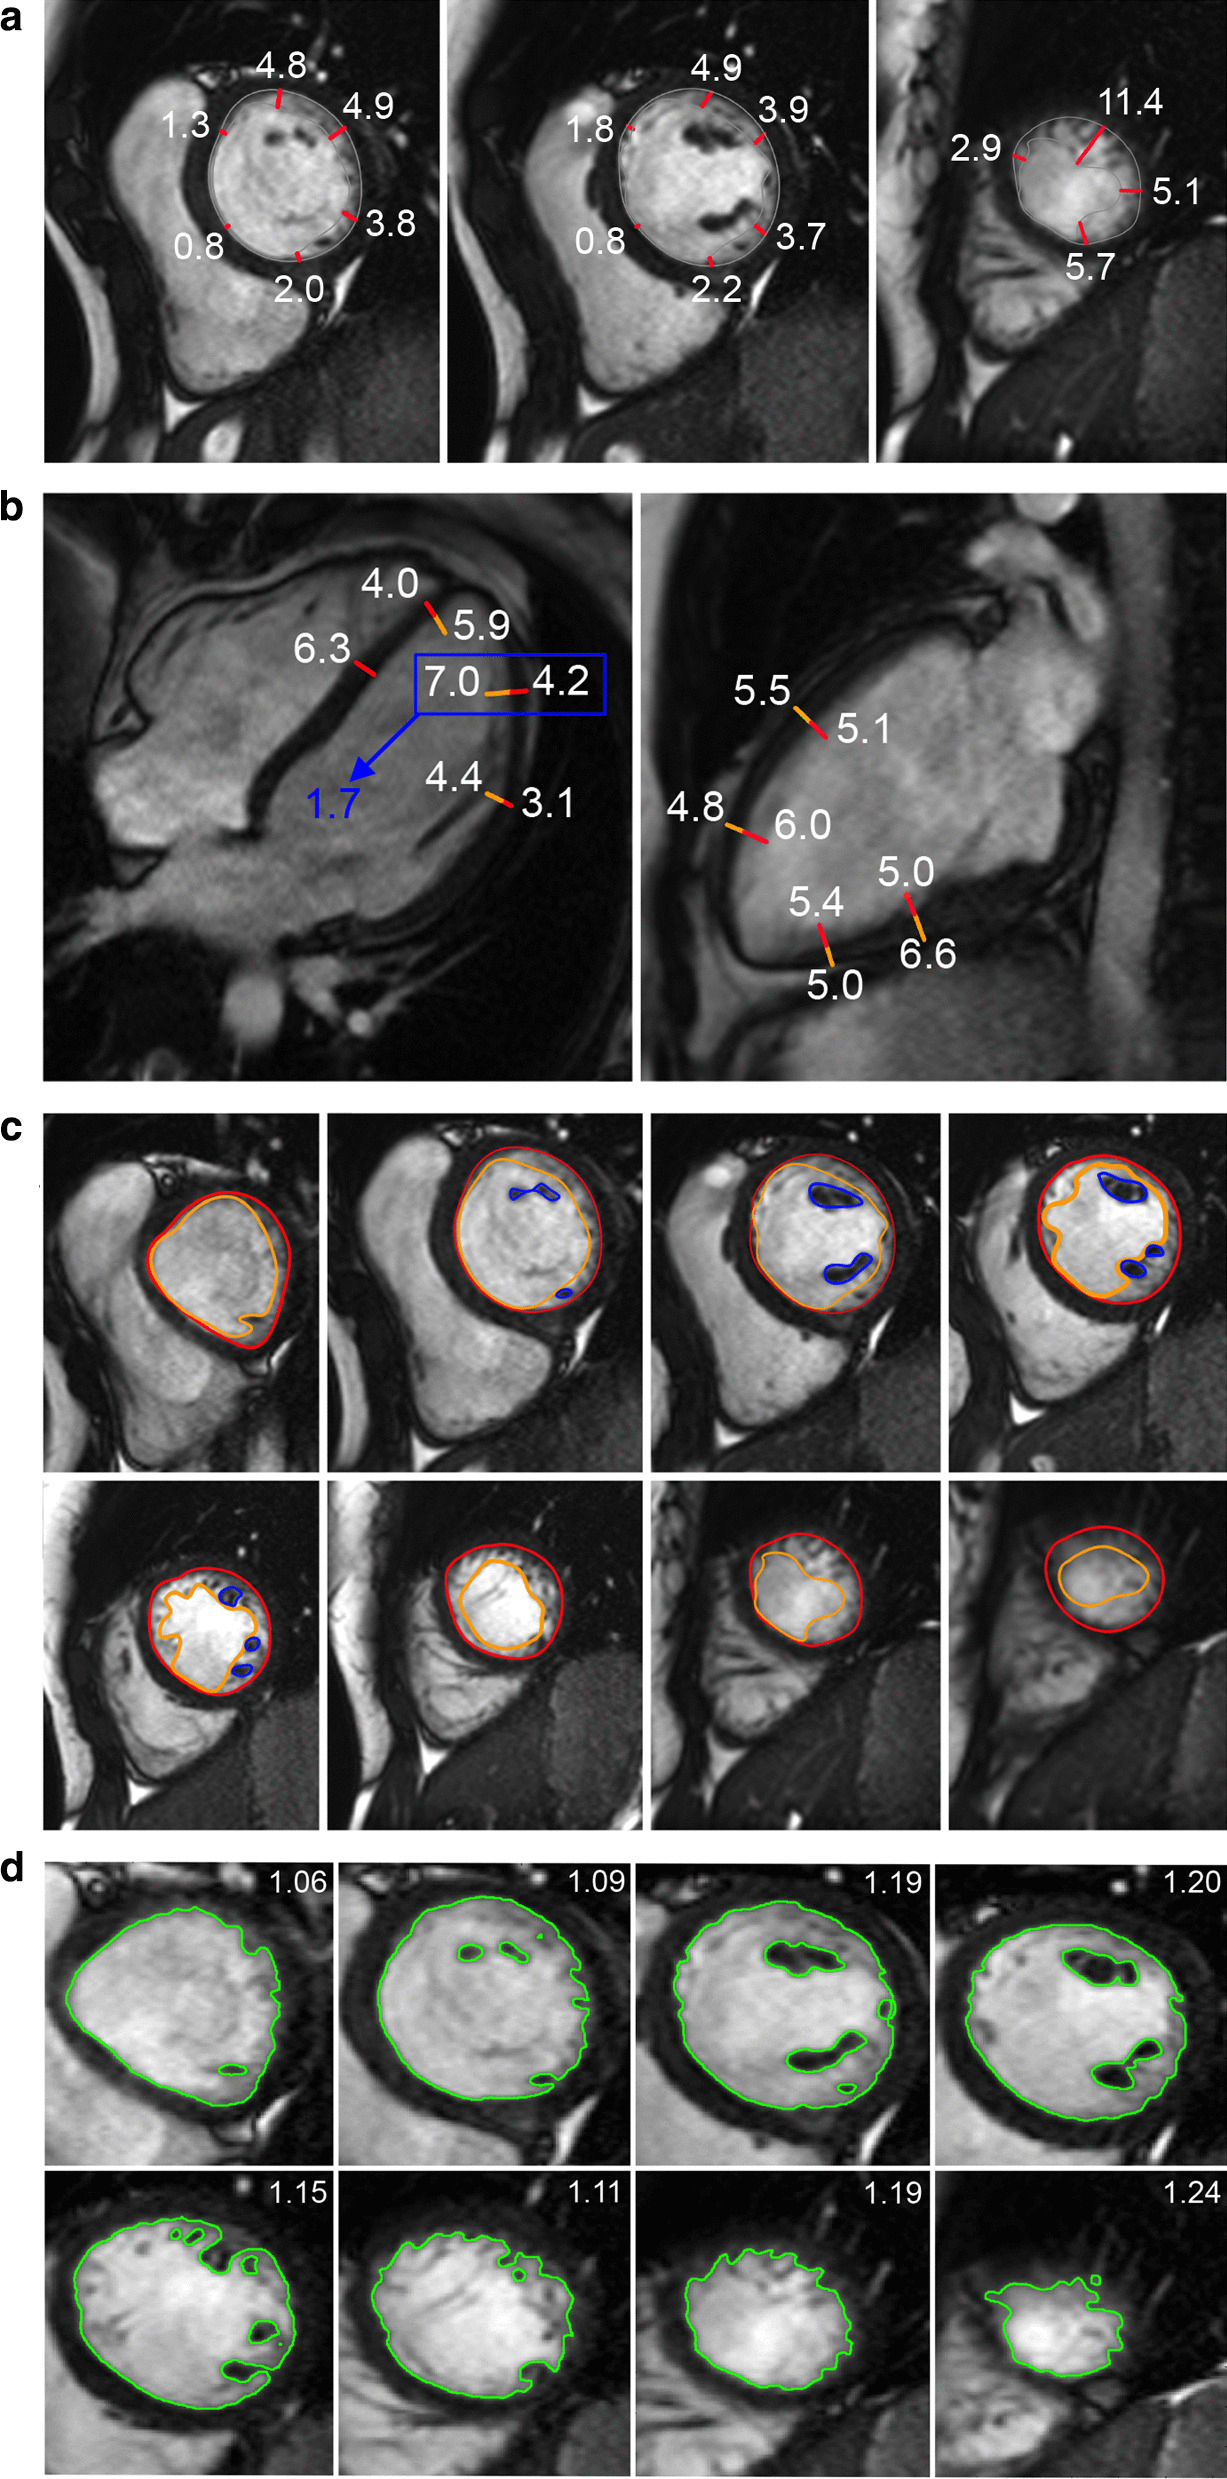

CMR analysis methods

In this review LV myocardial thickness refers to measurements of the thickness of the compact LV myocardium obtained at end-diastole (Fig. 7). Papillary muscles and trabeculations are excluded from measurement of the thickness of the compact LV myocardium.

Fig. 7.

Example of measurement approaches for LV trabeculation. a End-diastolic thickness (in mm) of trabeculation according to the methodology in [56]: 3 slices representing base, mid and apex were selected from within the entire LV stack; trabeculated myocardial thickness was measured per slice; segment 17 excluded from analysis; authors do not clarify whether papillary muscles had been included or excluded from the trabecular measurement—in this reproduction we have excluded papillary muscles. b Maximal non-compacted (NC, red lines)/compacted (c, orange lines) wall thickness ratio according to the methodology in [61]: papillary muscles that were clearly observed as compact tubular structures were not included in the measurements; measurements in mm are shown in white and the maximal NC/C parameter highlighted in blue. c Trabeculation mass according to the methodology in [12]: the endocardial contour (red) was manually drawn; the trabecular contour (orange) was automatically segmented and papillary muscles (blue) that were included in the compact myocardial mass, were semi-automatically segmented; all slices of the LV short axis stack were analyzed. d Fractal dimension according to the methodology in [60]: using a semi-automatic level-set segmentation with bias field correction; all slices of the LV short axis stack are analyzed except for the apical slice; fractal dimensions per slice reported in the top right corner

CMR methods used to assess LV trabeculation (Table 28) are based on the bSSFP technique to leverage on the blood-myocardial contrast it provides. The key methods are illustrated in Fig. 7.